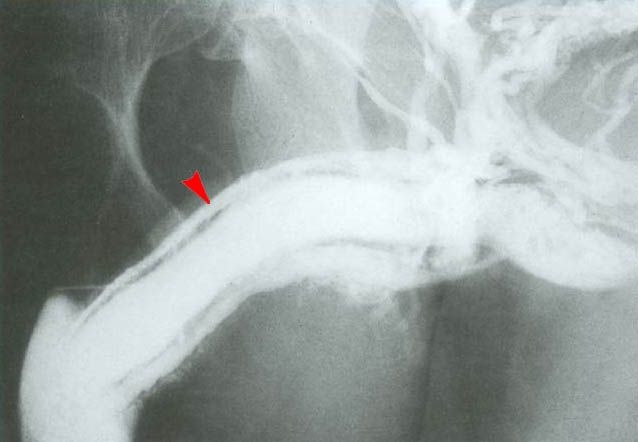

Для более точной диагностики могут быть назначены дополнительные исследования. Ультразвуковое исследование (УЗИ) является одним из наиболее распространенных методов, позволяющим визуализировать повреждения тканей и определить степень травмы. В некоторых случаях может потребоваться магнитно-резонансная томография (МРТ) для более детального изучения состояния полового члена и окружающих структур.

Если есть подозрение на повреждение уретры, может быть выполнена цистоскопия — процедура, позволяющая оценить состояние уретры изнутри. Это особенно важно, так как повреждение уретры может привести к серьезным осложнениям, таким как стриктура или свищи.